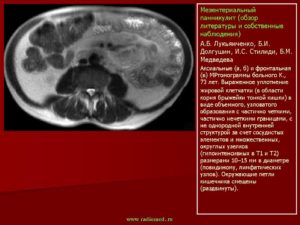

“Золотым стандартом” диагностики мезентериального панникулита считают магнитно-резонансную томографию и компьютерную томографию.

В результате исследования появляется возможность увидеть все деструктивные изменения структуры брыжейки, подкожно-жировой клетчатки, очаги уплотнения, фиброзной ткани и ограниченных опухолей.

Посредством МРТ или КТ можно своевременно выявить предраковые изменения вовлеченных в патологический процесс тканей.